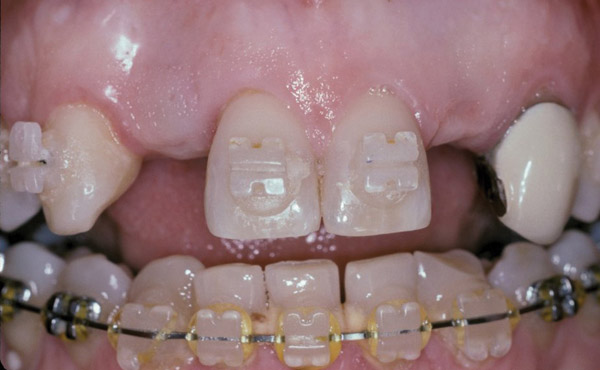

Figure 1  Initial presentation. Teeth Nos. 8 and 9 had internal and external resorption and were deemed hopeless. Recession of 4 mm was associated with tooth No. 9.

Figure 1

Figure 2  The orientation of the healing abutments after the patient had undergone extraction, guided bone regeneration, and implant placement. Note the wide spacing between the central incisor implants.

Figure 2

Figure 3  Periapical radiograph of implants in the Nos. 8 and 9 sites 3 years after placement. A bony peak was still present between the implants due to successful guided bone regeneration and favorable fixture spacing.

Figure 3

Figure 4  Final restoration of implants in the Nos. 8 and 9 sites 3 years after placement. Note the short central papilla regardless of the presence of bone. Restoration courtesy of Dr. Alan Goldberg.

Figure 4

Figure 5  A naturally low smile line hid the clinical “black triangle” from view.

Figure 5